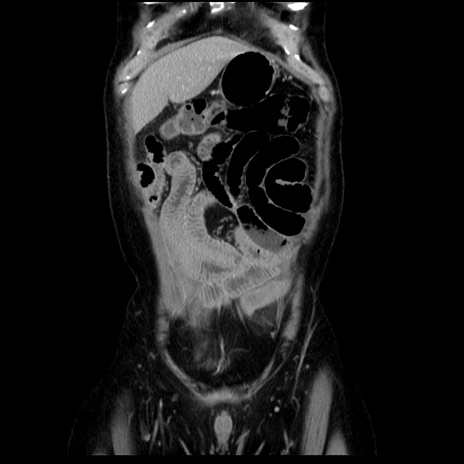

横断像

【症例】40歳代男性

【現病歴】2日前から胃痛あり。徐々に周期的な激痛に変化した。本日になっても激痛があるため受診。

【身体所見】意識清明、BT 38-39℃台あり、腹部:膨満、やや硬、右下腹部に圧痛あり。

【データ】WBC 8500、CRP 23.26